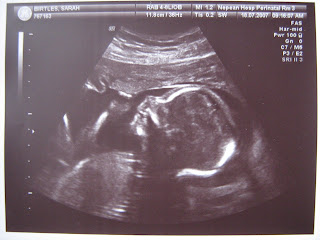

19 Weeks

We are 19 weeks into pregnancy, almost half way and everything is looking fine. I am growing, Squeaky is growing, Phill is about the same.

We have had our second and last ultrasound. It was quite a full house with me on the bed, Mum and Phill watching the screen and the lady performing the ultrasound! I am feeling a lot bigger, most pants and skirts don't fit now but Mum bought me some great new tops so I have room to grow now!